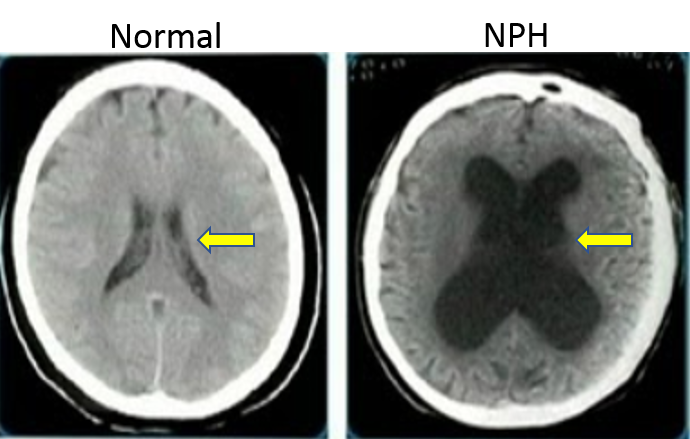

Research by Mark Johnson Provides Insights into Origins of Idiopathic Normal Pressure Hydrocephalus

more information...

New Research Grant to Study Normal Pressure Hydrocephalus